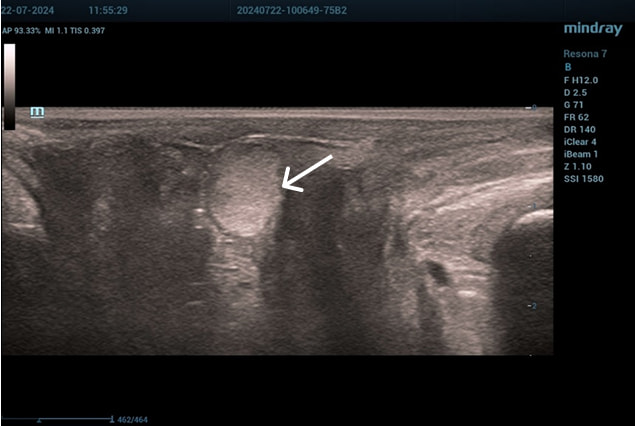

Осмотр: периуретрально визуализируется мягко-эластичное образование размерами 0,5×0,5 см.

Диагноз: хронический цистит (посткоитальный). Дистопия уретры. Опущение передней стенки влагалища I степени. Состояние после периуретрального введения геля на основе гиалуроновой кислоты.